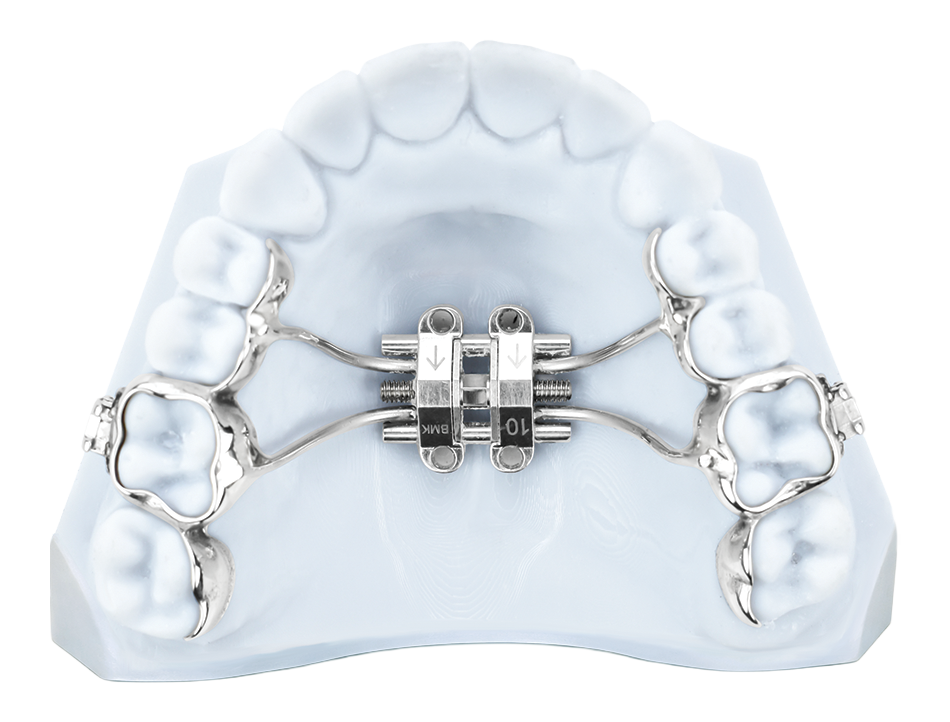

MSE MARPE

This MARPE configuration offers a streamlined approach using pre-fabricated screws with integrated eyelets. Appliance fabrication is based on palatal anatomy and may incorporate traditional or 3D printed bands, providing a reliable and efficient solution for appropriate cases.

- DMAX With MSE Screw – Includes 4 Eyelets

- Distal Jet With MSE Screw – Includes 4 Eyelets

- Tiger / Power Screw – Includes 2 Eyelets

- Super Screw – Includes 2 Eyelets

- DMJ – Includes 2 Eyelets

- Distal Jet – Includes 2 Eyelets